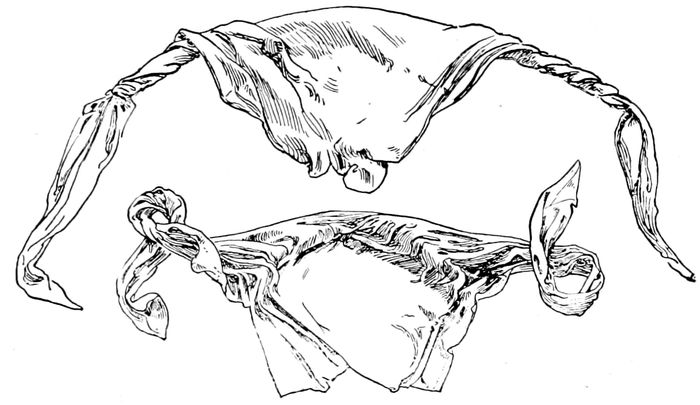

Abdominal binder with crosspiece to hold vulvar pads |

100 |

| |

| 1432. |

T-binder, used in all cases after the fifth day post partum |

100 |

| |

| 33. |

Breast binder |

101 |